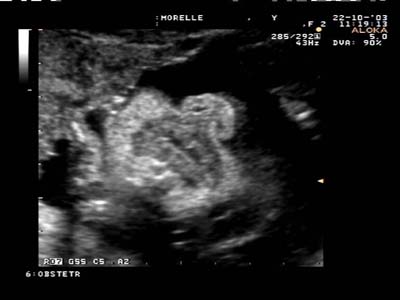

Intégrité de la lèvre supérieure